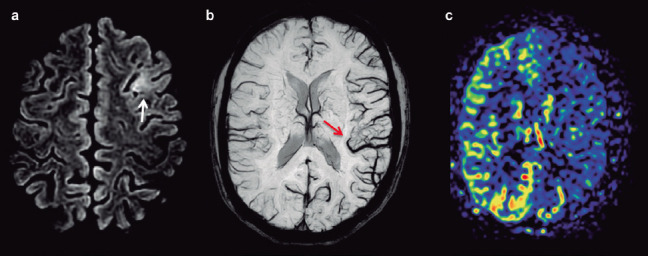

[Hemiplegic migraine: classic findings in a rare pathology].